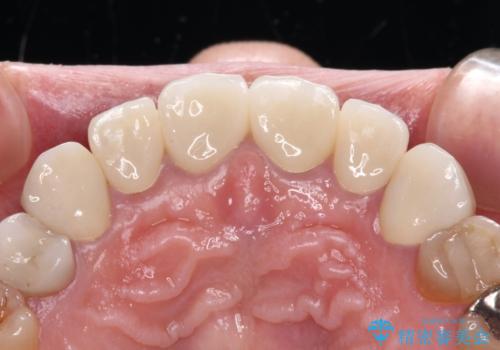

長年前歯の色の違いに悩んでいらっしゃったようですが、仮歯に変えた時点で統一感のある白さとなり喜んで頂きました。

わずか1ヶ月の間にとても自然な仕上がりのセラミッククラウンが装着され、患者様には大変満足していただきました。